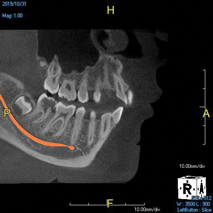

(4.) In a CBCT image axial view, the MB1 and MB2 canals are readily visible in tooth No. 14, and in the coronal view, these two separate canals can be seen to merge into a single apical opening.

Figure 4

(5.) In a CBCT image axial view, the MB1 and MB2 canals are readily visible in tooth No. 14, and in the coronal view, these two separate canals can be seen to merge into a single apical opening.

Figure 5